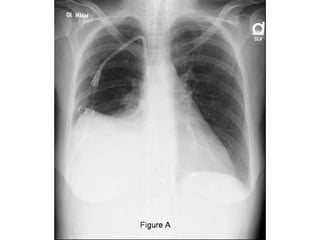

RADIOGRAPHIC EXAMINATION

• 75 mL-subpulmonic space without spill over, can

obliterate the posterior costophrenic sulcus,

• 175 mL is necessary to obscure the lateral

costophrenic sulcus on an upright chest

radiograph

• 500 mL will obscure the diaphragmatic contour

on an upright chest radiograph;

• 1000 ml of effusion reaches the level of the

fourth anterior rib,

• On decubitus radiographs and CT scans, less than

10 mL.